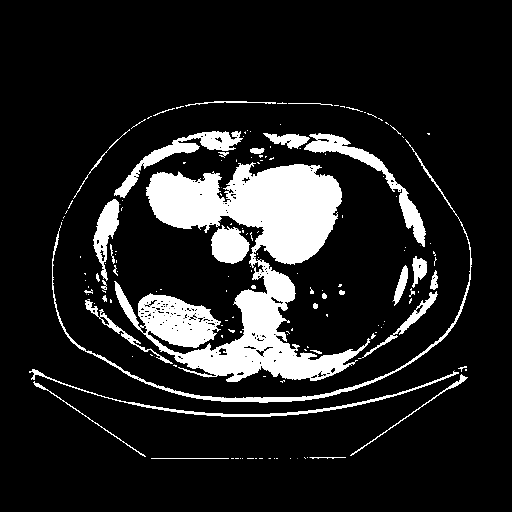

Generated VENOUS CT scan (A→B translation)

Full window (WL 1023.5, WW 4095 β†’ Low βˆ’1024, High +3071)

Actual HU range: [-1024.0, 3071.0]